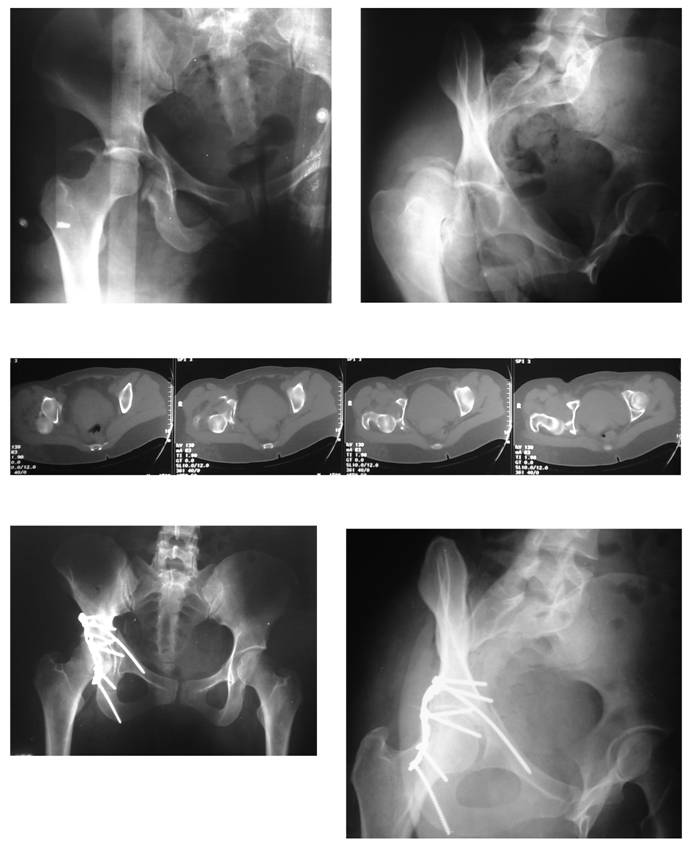

Figure 1

Pre-operative radiographs and CT scan, and postoperative radiographs of a patient (31 y/o female, road-traffic accident, unrestrained) who had fixation of the anterior component of the transverse acetabular fracture with an extra-long small fragment cortical screw ('home-run screw'). Note that the long screw bends as a result of the intimate contact with the pelvic brim. Follow-up duration of 18 months.